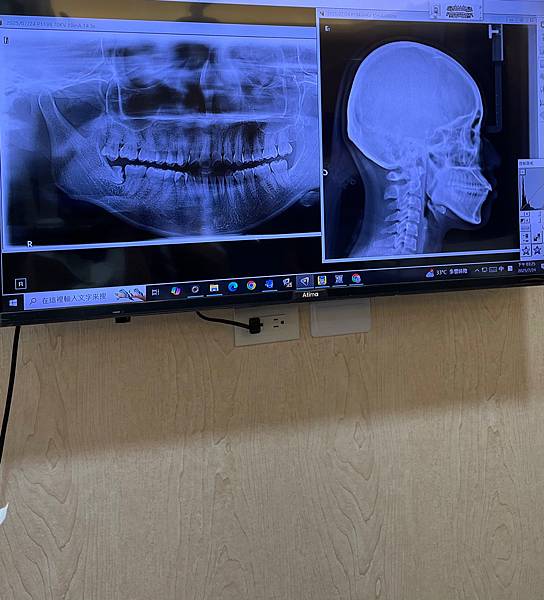

設備真的很新,過程快又舒適,通常拍完X光能馬上就能在螢幕上看到清楚的牙齒影像。

(此為示意圖,非本人)